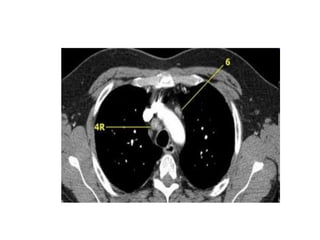

Haïch tröôùc maïch maùu -3A.

Haïch caïnh khí quaûn döôùi -4R.

4. HAÏCH CAÏNH KHÍ QUAÛN DÖÔÙI

Naèm döôùi ñöôøng ngang veõ tieáp tuyeán bôø treân

cung ñoäng maïch chuû.

4R-Haïch naèm beân (P) ñöôøng giöõa khí quaûn.

4L-Haïch naèm beân (T) ñöôøng giöõa khí quaûn môû roäng ñeán pheá quaûn